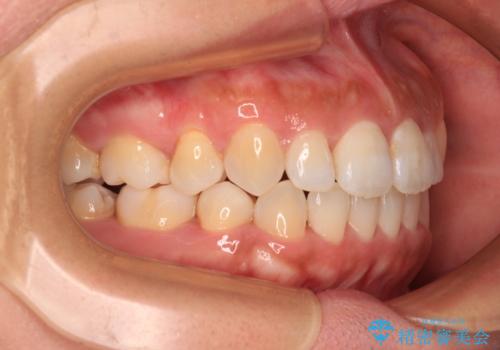

右上と左下の小臼歯が1本ずつ欠損しており、奥歯の咬み合わせが乱れている状態でした。

骨格的な左右差があり、上下正中をぴったり合わせることは難しく、奥歯の咬み合わせの調整にも時間がかかりましたが、きれいに整えることができました。